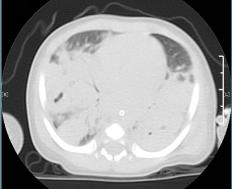

患儿入院后的肺部CT显示:两肺感染性病灶并多发肺脓肿形成。其肺部面临脓肿的侵蚀及炎症的破坏下能募集到的肺部有效通气极为有限,同时发热仍间断的出现,要在造成严重并发症之前,治疗在争分夺秒的同时进行。

治疗前